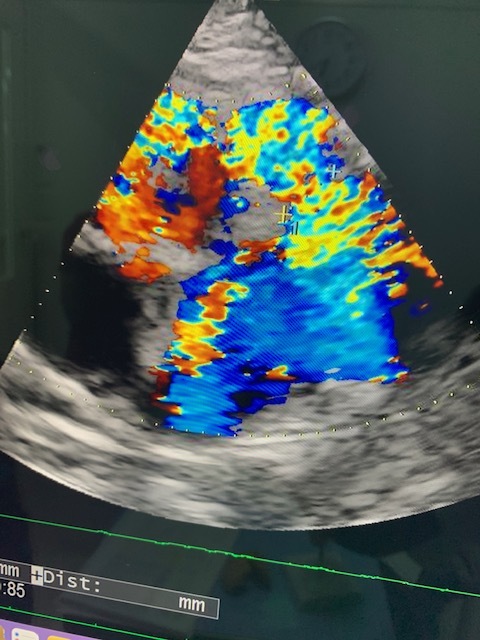

※術後、腹部エコーです。真ん中右部分(+付近)を

バンディン術をしております。

肺動脈回りを白い帯みたいな物で回し、血圧・酸素濃度(Spo2)を

確認しながら帯を少し縛りながら調整をして限界手前で、帯を固定しました。